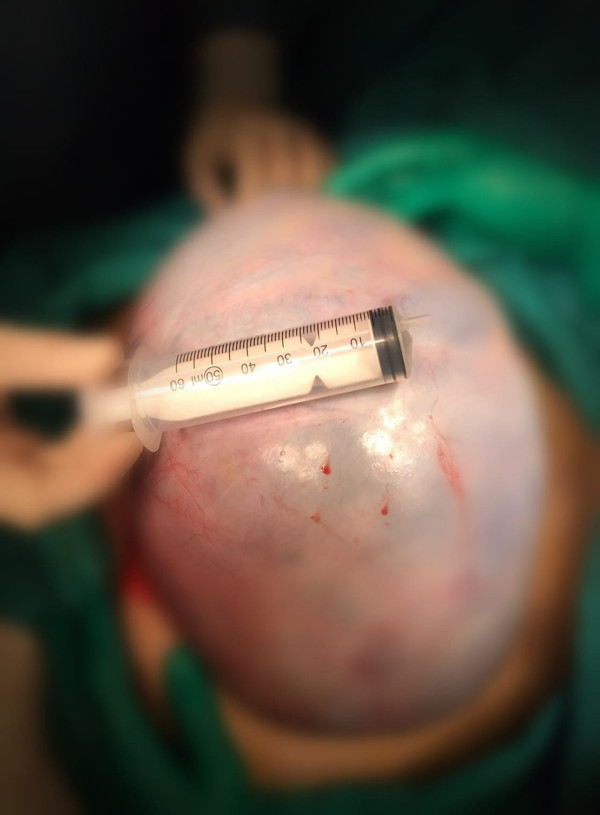

ANTALYA'da karın ağrısı şikayetiyle hastaneye giden 54 yaşındaki Havva Yılmaz'ın yumurtalığından 20 kilogram ağırlığında, büyüklüğü 40 santim çapında kitle olduğunu belirlendi. Yapılan ameliyat sonrası Yılmaz, sağlığına kavuştu.

Abone olAlanya’da yaşayan Havva Yılmaz, (54) isimli şiddetli ağrı, şişkinlik ve bulantı şikayetiyle Alanya Alaaddin Keykubat Üniversitesi Eğitim ve Araştırma Hastanesine başvurdu. Yapılan tetkikler sonucu Yılmaz’ın yumurtalığında 20 kilogram ağırlığında 40 santim gelen kitle olduğunu saptandı.

Yılmaz bunun üzerine Kadın Hastalıkları ve Doğum Uzmanı Op. Dr. Muhammet Serhat Yıldız ile Uzman Öğr. Üyesi Dr. Meral Tuğba Çimşir ve Op. Dr. Büşra Yıldız tarafından ameliyata alındı. Başaralı geçen ameliyat Yılmaz, sağlığına kavuştu. Bir süre normal odada kalan Yılmaz taburcu oldu.

Başarılı ameliyat sonrası hastayı serviste ziyaret eden Dr. Öğr. Üyesi Çimşir, “Bir buçuk saat süren ameliyatımız oldukça başarılı geçti. Kendisini sağlığına kavuşturduğumuz için onurlu ve gururluyuz” diye konuştu.

Op. Dr. Muhammet Serhat Yıldız ise şunları söyledi: ”Havva Hanımda yapılan tetkikler sonucunda abdominal bir kitle gördük. Hastamızın onayını alarak doktor arkadaşlarla birlikte ameliyat kararı aldık. Kitlenin büyüklüğü ve yeri nedeniyle operasyonun zorlu geçeceğini biliyorduk. Başından beri doğru kararlar alarak başarılı bir iş çıkardık“.